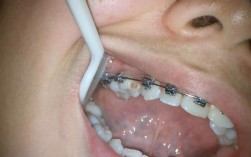

虽然阻抗中心是牙齿的固有属性,但正畸治疗中通过矫治器(如托槽、带环)施加的力的大小、方向及作用点(施力点),会改变牙齿实际移动的“等效阻抗中心”,当托槽位置过高(靠近切缘)时,施力点偏离天然阻抗中心,牙齿易发生倾斜移动而非整体移动;若通过额外装置(如舌侧扣、种植体支抗)调整施力点,使其通过天然阻抗中心,则可实现更高效的整体移动。